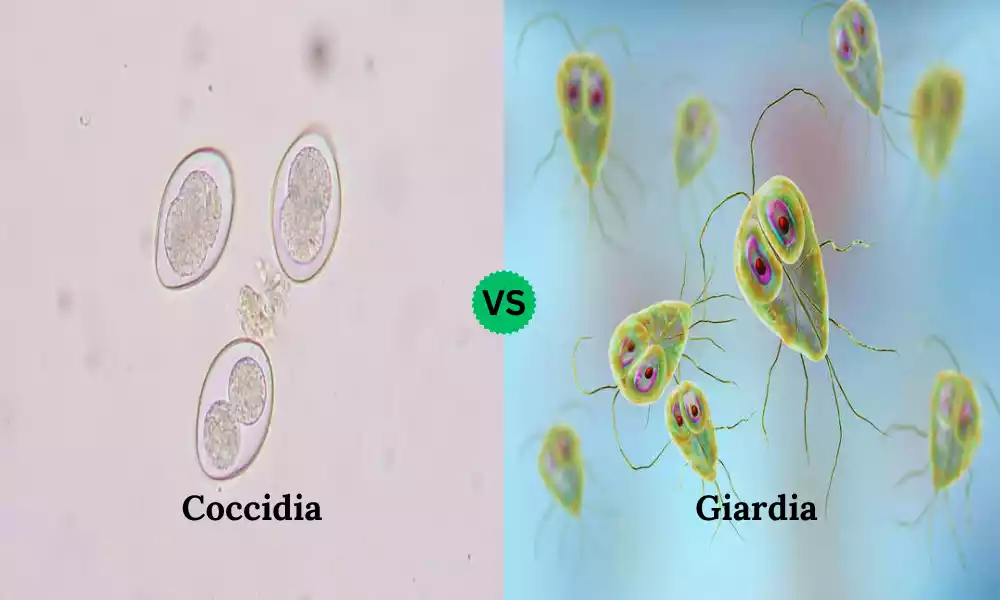

Coccidia and Giardia are two common intestinal parasites that affect animals, including dogs and cats. These microscopic organisms can lead to gastrointestinal issues and discomfort in pets. Coccidia and Giardia infections can cause symptoms such as diarrhea, vomiting, and weight loss. Proper understanding, diagnosis, and treatment are crucial to ensure the well-being of our furry companions.

Explanation of Coccidia

Coccidia is a type of protozoan parasite that primarily infects the gastrointestinal tract of animals, including mammals, birds, and reptiles. They belong to the family Eimeriidae and are part of the phylum Apicomplexa, which includes other parasitic organisms like Plasmodium (causative agent of malaria) and Toxoplasma (causative agent of toxoplasmosis).

Characteristics of Coccidia

- Single-Celled Organisms: Coccidia are single-celled organisms, meaning they consist of a single cell that performs all necessary functions for their survival and reproduction.

Explanation of Giardia

Giardia is a genus of microscopic, flagellated protozoan parasites that can infect the digestive systems of various animals, including humans. Giardia duodenalis, formerly known as Giardia lamblia or Giardia intestinalis, is the species most commonly associated with human infections.

Characteristics of Giardia

- Flagellated Organisms: Giardia parasites possess hair-like structures called flagella, which they use for movement and attachment to the host’s intestinal lining.

- Two Morphological Forms: Giardia alternates between two forms in its lifecycle: the dormant cyst form, which is resistant to environmental conditions, and the active trophozoite form, which is found within the host’s intestine.

Comparison Table of Coccidia and Giardia

Here’s a comparison table highlighting the key differences between Coccidia and Giardia infections:

| Aspect | Coccidia | Giardia |

|---|---|---|

| Classification | Protozoan parasites belonging to the family Eimeriidae | Protozoan parasites belonging to the genus Giardia |

| Morphology | Single-celled organisms | Flagellated organisms |

| Infection Route | Fecal-oral transmission via oocysts | Fecal-oral transmission via cysts |

| Lifecycle | Complex, involves asexual and sexual stages | Alternates between cyst and trophozoite stages |

| Host Specificity | Species-specific; various species infect different animals | Can infect a wide range of animals, including humans |

| Clinical Symptoms | Gastrointestinal disturbances, diarrhea, dehydration | Gastrointestinal symptoms, diarrhea, abdominal cramps |

| Attachment to Host | Parasites reside within host’s cells | Parasites attach to intestinal lining |

| Diagnostic Methods | Fecal flotation, microscopic examination | Microscopic examination, rapid tests, PCR |

| Treatment | Anticoccidial medications | Antigiardial medications |

| Prevention | Improved hygiene and sanitation | Clean water sources, hygiene practices |

| Public Health Concern | Common in animal husbandry and farming | Relevant in areas with poor sanitation and water quality |

This table provides a concise comparison, there may be additional details that can be included depending on the level of depth and specificity you want to achieve in your content.